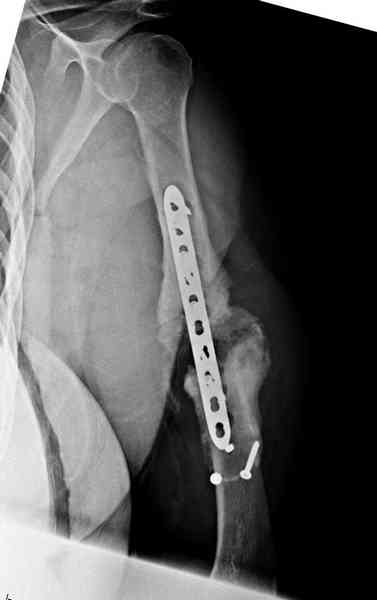

Хотя сам не стороннник применения более массивных

имплантов для плеча, но для этого случая сделали

исключение. На снимке 4А диаметр мягких ткани около 20 см, при весе больной более 135 кг, и также выступление Андрея Волны подстегнуло к применению более массивной 4.5 мм локинг пластины.

А для стимулирования мы применили массу из состава:

OP1 с деминерализованной костью, добавив к ним еще

красную часть, приготовленную из крови больной.

Взятая перед операцией кровь в количестве 80 мл

провели через центрифугу и без сывороточной части

красную матрицу добавили к остальным.

С такой массой наверное ложный сустав "over killed", но надеюсь, что-то из них при такой фиксации окажет стимулирующее действие.